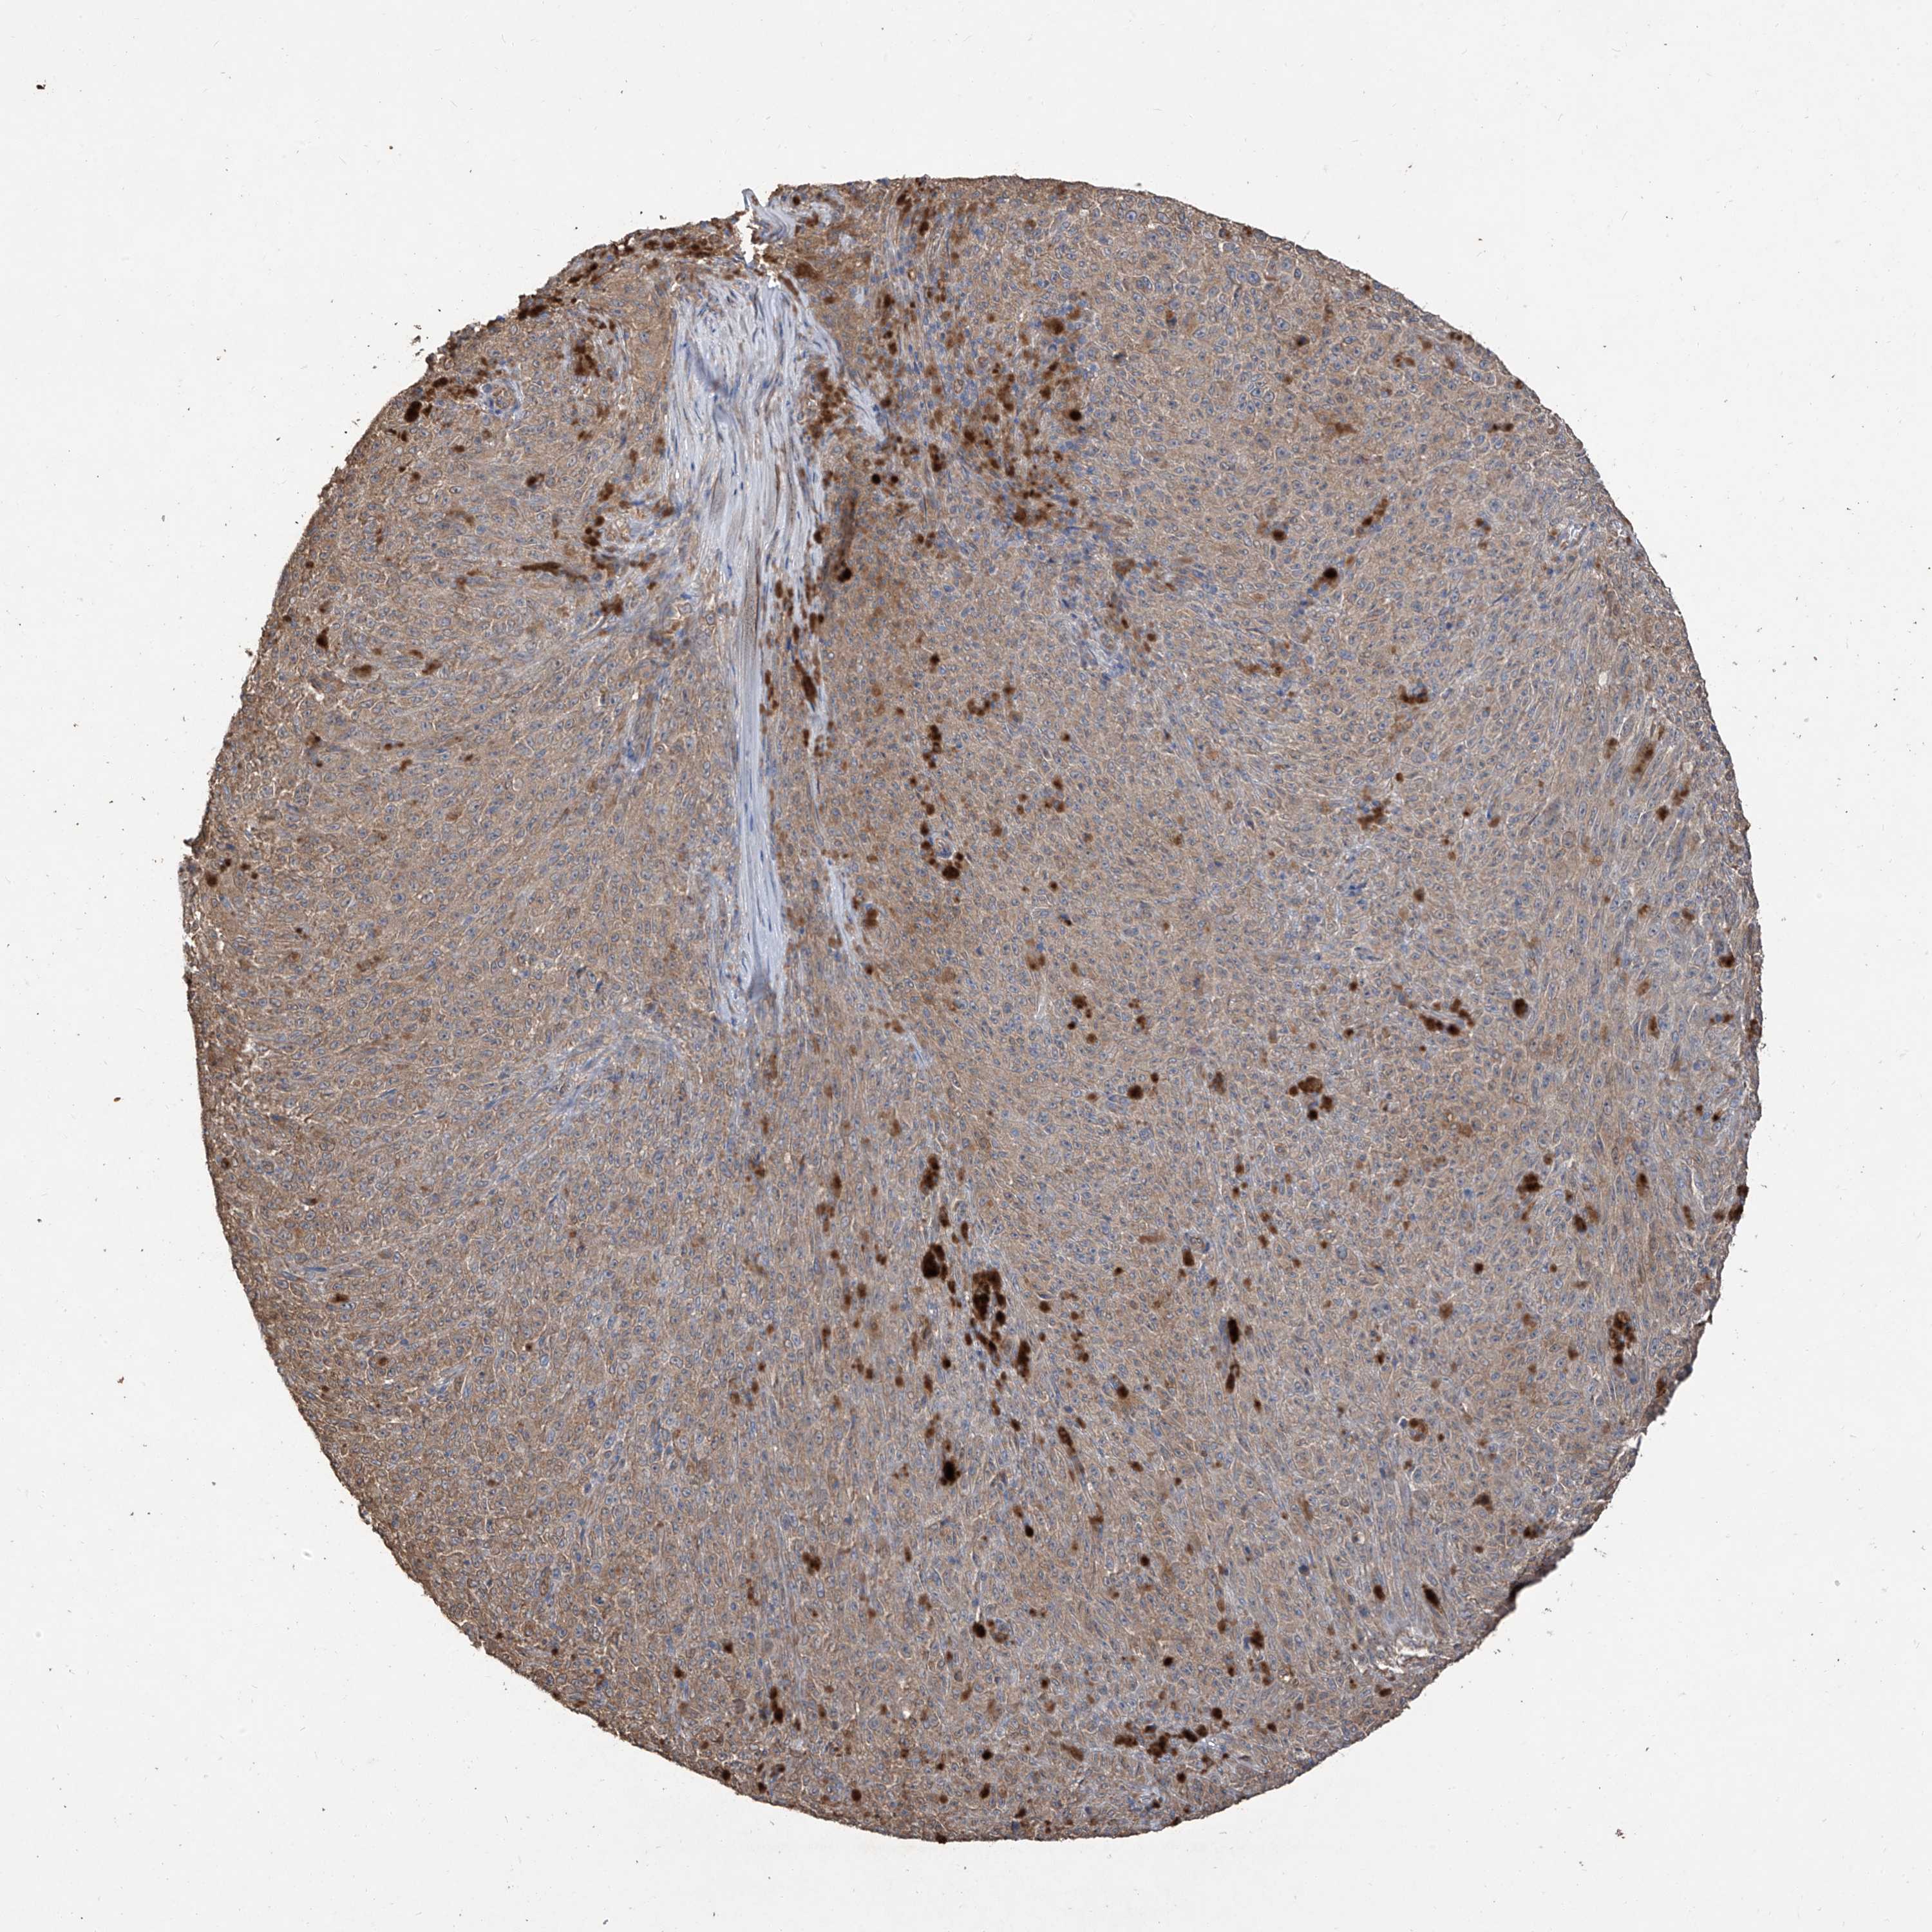

MELANOMA - Protein expressioni

A mouse-over function shows sample information and annotation data. Click on an image to view it in a full screen mode. Samples can be filtered based on level of antibody staining by selecting one or several of the following categories: high, medium, low and not detected. The assay and annotation is described here.

Note that samples used for immunohistochemistry by the Human Protein Atlas do not correspond to samples in the TCGA dataset.

Antibody stainingi

Antibody staining in the annotated cell types in the current human tissue is reported as not detected, low, medium, or high, based on conventional immunohistochemistry profiling in selected tissues. This score is based on the combination of the staining intensity and fraction of stained cells.

Each image is clickable and will lead to virtual microscopy that enables deeper exploration of all samples and also displays staining intensity scores, fraction scores and subcellular localization as well as patient and tissue information for each sample.

Antibody HPA030981

Staining

High

Medium

Low

Not detected

Intensity

Strong

Moderate

Weak

Negative

Quantity

>75%

75%-25%

<25%

None

Location

Nuclear

Cytoplasmic/membranous

Cytoplasmic/membranous,nuclear

Malignant melanoma, NOS

Malignant melanoma, Metastatic site